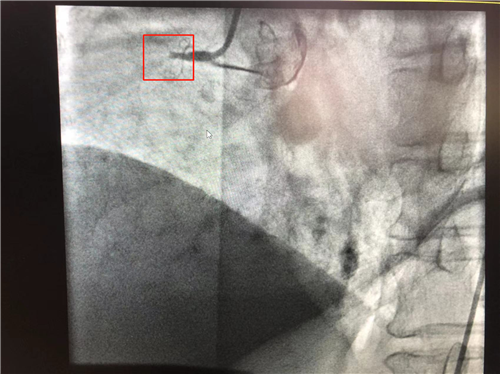

時間就是心肌,時間就是生命。導管室內,心血管內科副主任徐先進、主任助理農彥林已然待命,病人一到,團隊立即為其行深靜脈穿刺泵入血管活性藥物等,情況緩解后,行多體位冠狀動脈造影,確認RCA(右冠狀動脈)近端完全閉塞。經家屬同意,在汪念東院長的指導下,徐先進、農彥林、張星為患者行經皮冠狀動脈球囊擴張成形術+經外周靜脈穿刺中心靜脈置管術。術中,張奶奶再次出現室顫,心血管內科團隊臨危不亂,立即予以300焦電除顫搶救,患者竇性心律恢復。隨后,球囊擴張為其置入心臟支架,復查造影顯示血管恢復暢通,無明顯夾層,殘余狹窄不到10%。術后,張奶奶血壓偏低,轉入ICU無創(chuàng)呼吸監(jiān)護,2天后轉回心血管內科護理。

術前:右冠近端閉塞